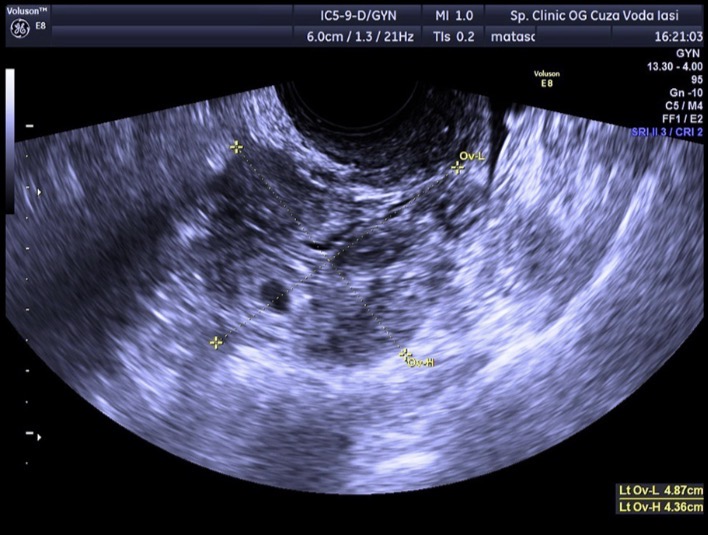

Figure 2. Трансвагинальное УЗИ: гетерогенное образование слева с центральной кистозной полостью, окружённой гиперэхогенным ободком.